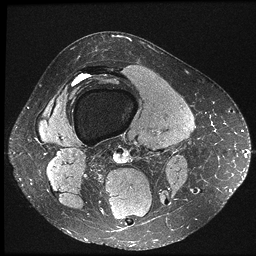

数据转换后的效果如下: